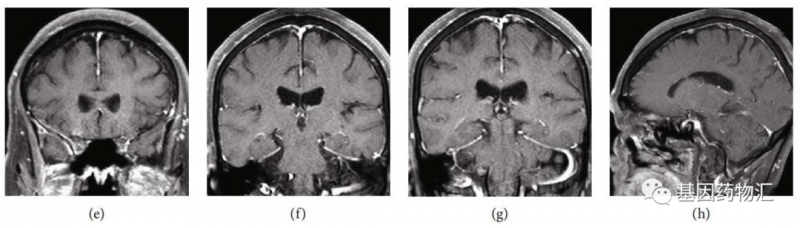

除了肺部的病灶,患者颅内的转移病灶也数量惊人,根据增强MRI的检查结果,病灶总共超过20个!属于非常典型的多发脑转移。

高龄、晚期、多发转移,这样的患者还有希望通过药物治疗达到缓解吗?事实上,在接受了仅仅5周的奥希替尼治疗之后,患者颅内的病灶,竟然完全消失了!

研究者据此指出,对于部分患者,尤其是将奥希替尼作为一线治疗方案的患者,脑部放疗完全可以推迟,甚至部分响应良好的患者根本不需要脑部放疗。

这说明,在某些特殊的情况下(比如患者可能很难耐受放疗,或颅内转移病灶数量过多等),可以考虑先使用奥希替尼治疗。如果患者对于药物的响应良好,很可能奥希替尼的治疗能够为脑部放疗提供条件,或者直接凭借药物治疗完全消除病灶。